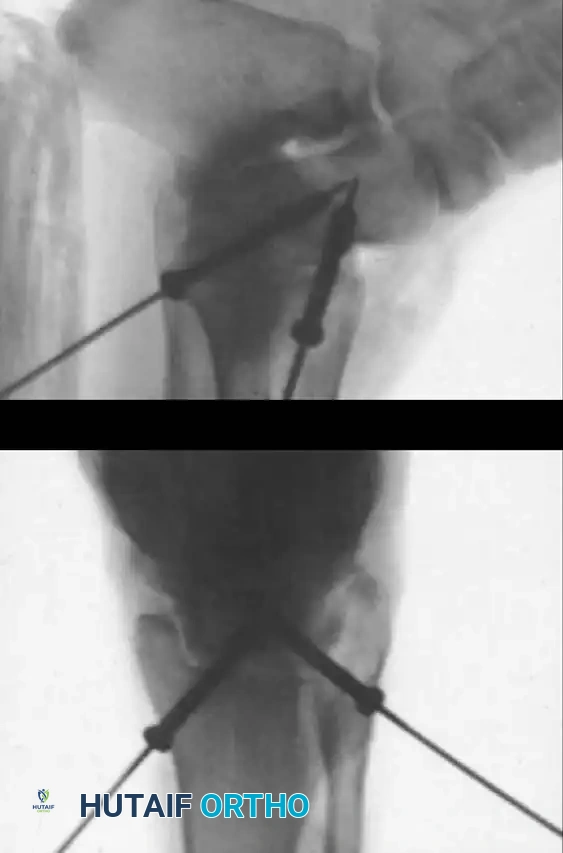

Transmalleolar Portals

As originally described by Guhl, transmalleolar portals are advanced techniques reserved for addressing osteochondral defects of the posterior-central portion of the talus that cannot be reached via standard portals.

Medial transmalleolar portal trajectory.

Lateral transmalleolar portal trajectory.

- Technique: These portals are established 2 to 3 cm proximal to the tip of the medial or lateral malleolus. Under direct arthroscopic visualization from an anterior portal, a 0.062-inch Kirschner wire is inserted using an anterior cruciate ligament (ACL) tibial guide for pinpoint accuracy. The wire is advanced across the malleolus to drill the chondral lesion. The ankle can be dynamically plantarflexed or dorsiflexed to allow drilling of the lesion in various locations.